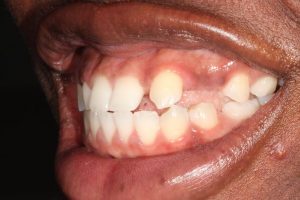

Upper Anterior Implants with Orthodontic Treatment

This patient was born with missing teeth and as a result the teeth that were present moved into these spaces. We started with orthodontic treatment (braces – undertaken by Dr Zaid Esmail) to move the teeth into the correct position and create the space needed for the dental implants. The implants were then placed towards the end of the braces treatment and the crowns fitted once the teeth were fully aligned.